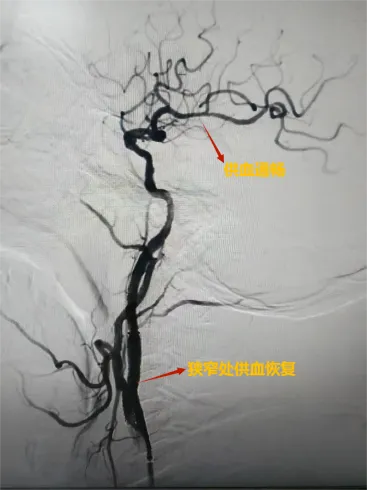

邵阳日报·邵阳新闻在线讯(通讯员 林海英)10月10日,神经内科一区收到了一封感谢信,来自一位因颈动脉狭窄进行了支架置入术的患者。患者从入院检查到完成手术康复出院仅用时三天,邵阳市中心医院神经内科介入团队让患者体验到了“微创手术+快速康复”的惊喜。

颅内动脉狭窄是导致缺血性脑卒中的重要原因,而支架植入术是有效的预防手段。该手术操作极其精细,容错率低。近年来,随着国家对于卒中防治体系建设的投入,该院神经内科介入团队手术量持续增长,技术的熟练度带来了手术成功率的显著提升和并发症发生率的明显下降。

以前人们只要听到“支架”二字,便会谈“支”色变,高昂的价格让人望闻却步。但近年来随着国家医保政策的变化以及高值医用耗材集采政策的实行,支架价格打破了价格壁垒,医生能更好地运用合适的技术与器械为患者服务,真正实现了“让技术回归医疗本质”。我们坚信,在政策与技术的双轮驱动下,神经内科团队将能为更多脑血管病患者守护住生命的蓝天。